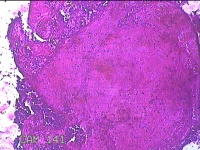

宫腔内容物

性别

女

年龄

临床诊断

一般病史

无

标本名称

大体所见

灰白暗红色不规则碎组织2.8x2x0.7cm一堆。

图2